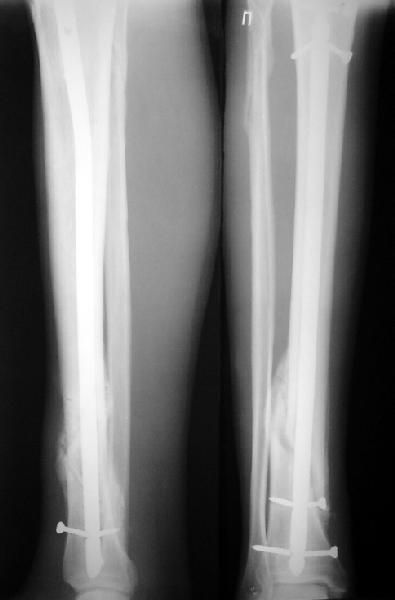

Как мне показать пример? Фото стоящего на одной оперированной конечности пациента? O! Пример, подвигнувший нас на некоторое изменение технологий. Пациент этот ходил с полной нагрузкой вопреки рекомендациям. В качестве подтверждения - сломанный проксимальный статический винт к 1 мес., а к 2 мес. - все остальные. Сейчас мы перешли на более fool-proof остесинтез.

На мой взгляд, на снимках, приведённых Вами - неправильно сростающийся перелом дистальной трети большеберцовой кости, состояние после остеосинтеза интрамедуллярным гвоздём.

Установка с медиальной стороны гвоздя в области дистального фрагмента дополнительного шурупа помогло бы Вам репонировать и удержать перелом в анатомическом положении, предотвратило варусную деформацию и смещение по ширине.

Let to express concerning technique of operation my opinion... Insertion of a screw to medial side of a nail in distal fragment would help you to reduction and to keep this fracture in anatomic position has prevented varus deformity and displacement on width. By the way, if it is possible send a postoperative picture.

Это наглядная демонстрация возможности ранней полной нагрузки при нестабильном по оси повреждении, причем не в самых благоприятных механических условиях - при плохом сопоставлении, со слабым фиксатором.